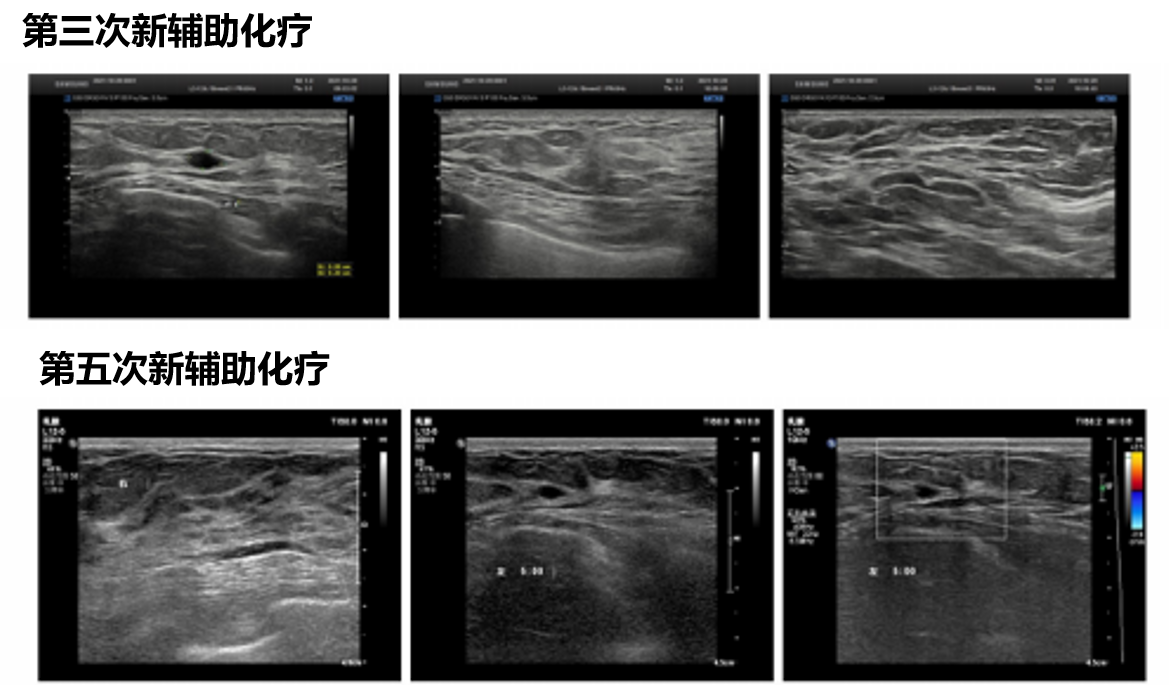

由于患者为三阳性乳腺癌,且伴有腋窝淋巴结转移,未见远处转移,因此推荐接受新辅助治疗,治疗方案为TCbHP。第3次和第5次新辅助治疗后,超声检查提示,左乳9-10点未见异常团块,双侧乳腺组织未见明显增厚,回声分布均匀,CDFI示未见异常血流信号。双侧腋下未见异常实质性光团,CDFI示血流信号未见异常。